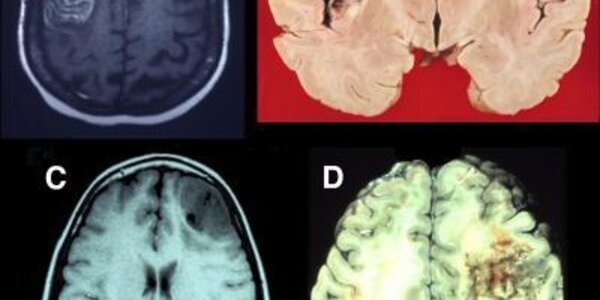

Studying Prefrontal Lobe Damage Unlocks Brain Mysteries

Until the last few decades, the frontal lobes of the brain were shrouded in mystery and erroneously thought of as nonessential for normal function—hence the frequent use of lobotomies in the early 20th century to treat psychiatric disorders. A review in Neuron highlights studies of patients with brain damage that reveal how distinct areas of the frontal lobes are critical for a person's ability to learn, multitask, control their emotions, socialize, and make real-life decisions.  Although fairly common, damage to the prefrontal lobes (also called the prefrontal cortex) is often…